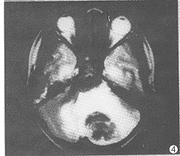

脑结核球(图3、4): 单发5例,多发7例,为脑质内大小不等、类圆形异常信号,最大者5cm×7cm,最小者0.5cm×1.0cm。T1WI呈低信号2例,等信号5例,等低混杂信号5例;T2WI呈等信号7例,等高混杂信号3例,等低混杂信号2例。增强扫描病灶边缘呈环状强化2例,呈弧形及结节状强化8例,无强化2例。

图3、4 结核性脑膜炎合并脑结核瘤。横断位T1WI平扫(图3)示

结核瘤呈中等信号为主,周边包膜呈弧形低信号影;

T2WI(图4)示结核瘤呈中等偏低信号为主,周围水肿呈片状高信号改变